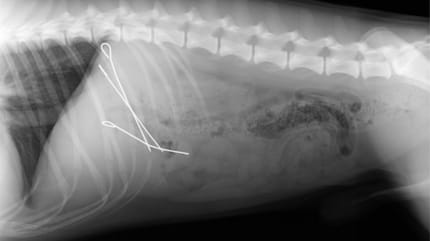

Radiographie d'un chien avec des piques à paupiettes

Là-bas, la technologie moderne fait enfin la lumière sur cette affaire. Lorsque la radiographie apparaît sur l'écran, il n'y a plus aucun doute. Le cliché montre l'estomac du « voleur » et, même pour un œil non averti, on y distingue très clairement trois piques à paupiettes.

La soirée s'est donc déroulée « un peu différemment que prévu » pour le chien et ses maîtres, comme l'a rapporté la clinique vétérinaire sur Facebook le 25 décembre 2025. En effet, peu de temps après, une opération d'urgence a été nécessaire pour retirer les piques en métal de l'estomac du chien.